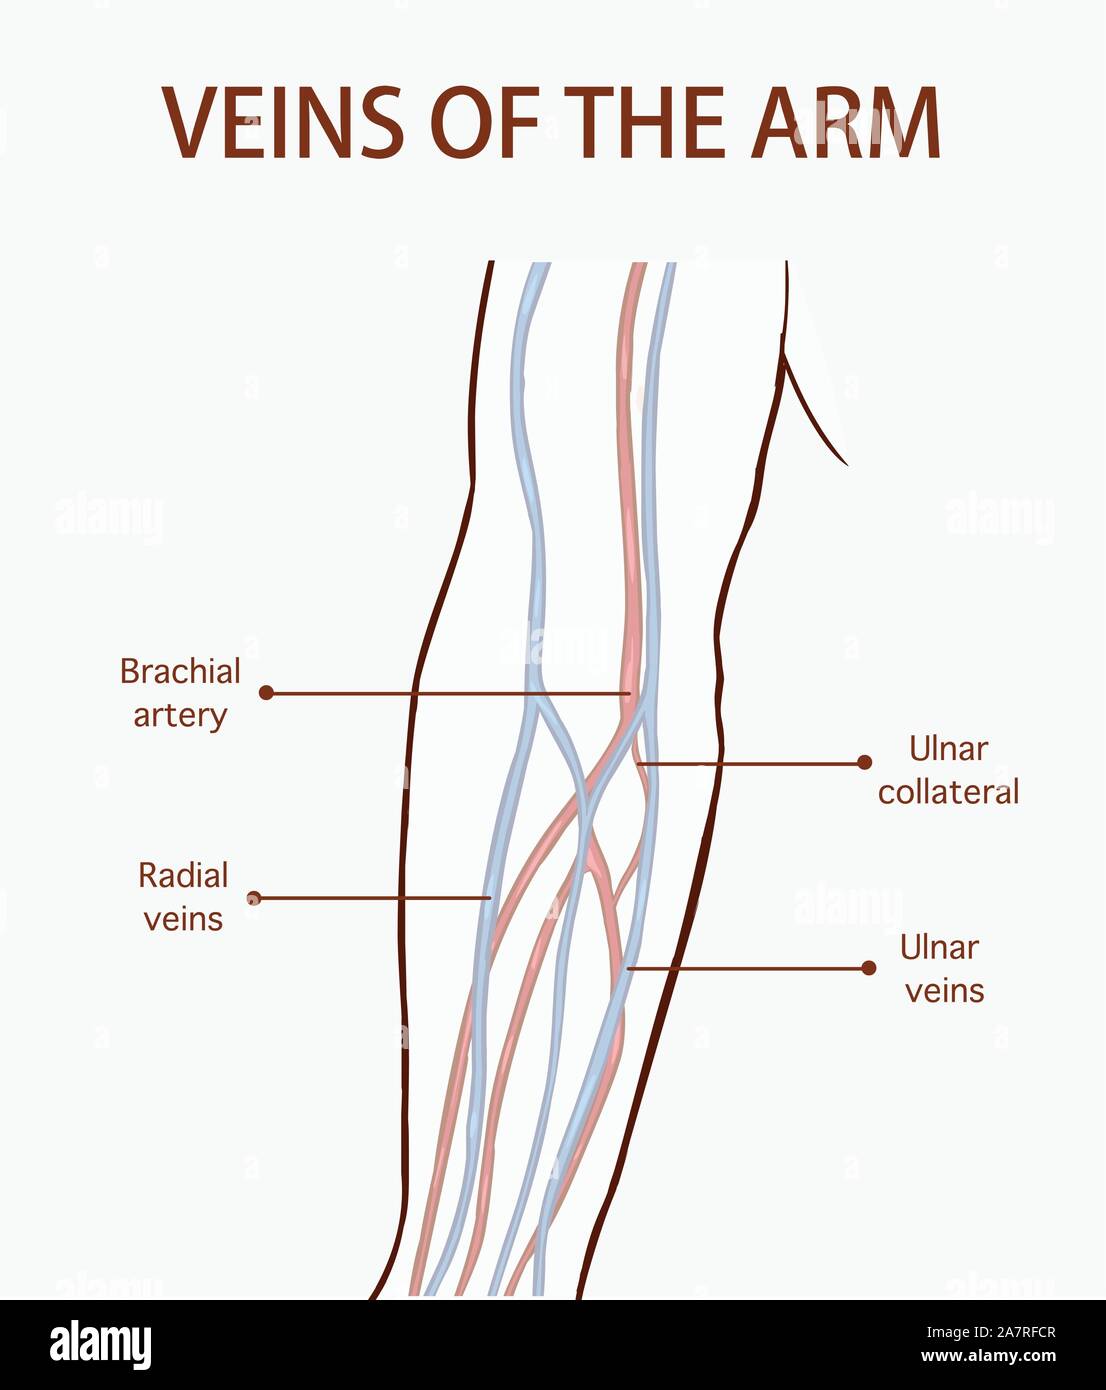

VEINS OF THE ARM - MEDizzy

medizzy.com